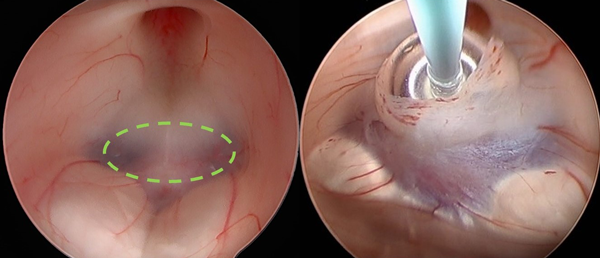

Se identifica el sitio óptimo para la ventriculostomía: espacio pre-mamilar. Se insufla bajo visión endoscópica el balón del catéter Fogarty N°4 dentro del III ventrículo con una jeringa de 1 cm3, de este modo se puede saber el sitio exacto donde se expande. Con dicho catéter, se procede a la fenestración roma con movimientos de rotación. Se insufla el balón de tal modo, que el ecuador del mismo coincida con el anillo de la fenestra. Se mantiene el balón insuflado por 10 segundos con 0.4 cm3 de aire (Figura 4).

Figura 4: Anatomía para una TVE. Izquierda: Vista panorámica del piso del III ventrículo con delimitación de la zona de fenestración segura a nivel del espacio pre-mamilar. Derecha: Fenestración propiamente dicha en zona segura con sonda Fogarty N° 4 e insuflación de balón.